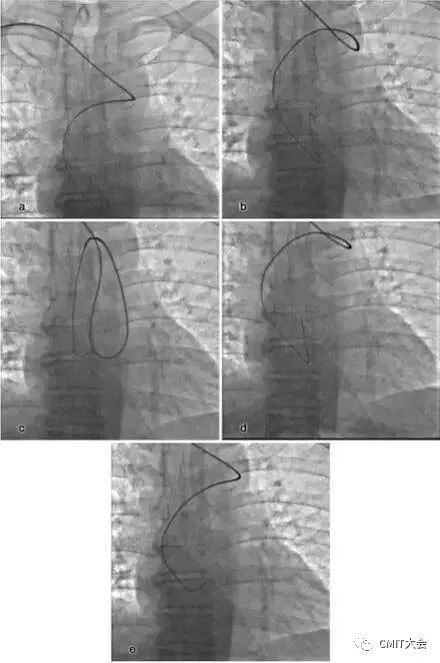

桡动脉迂曲在TRI中是一常见问题,约占3.8%~4.2%,桡动脉迂曲的部位在桡动脉近心端三分之一处,老年及女性患者的发生率要明显高于其他人群。根据桡动脉迂曲的形态可进一步将其细分“S”、“α”、“Ω”以及“Z”等多种类型,其中以“S”和“Ω”形迂曲最为常见,不同类型的桡动脉迂曲处理难度亦不相同,例如桡动脉“S”形迂曲的处理相对较为容易,其操作成功率要高于其它类型的桡动脉迂曲。

“S”

“α”

“Ω”